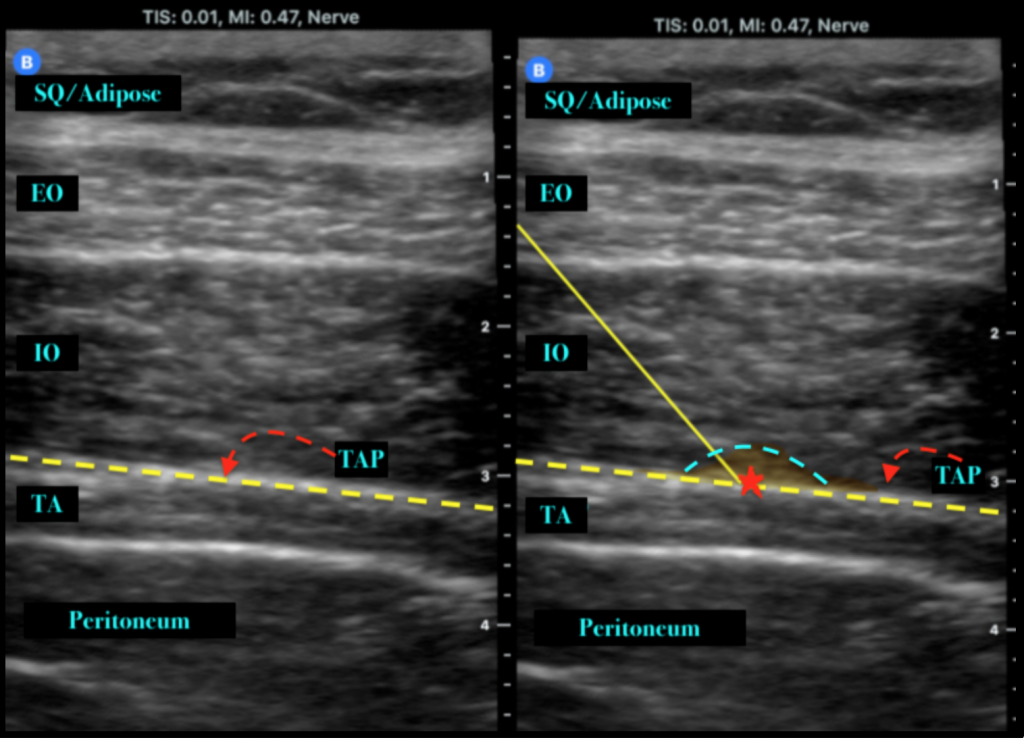

From www.pnbschool.com

TAP Images pnbschool How Long Does Tap Block Last Depending on the type of medicine used, a tap block will usually last for 12 to 36 hours. When performed with ropivacaine, the tap block has an analgesia duration of up to 24 hours, with an average duration of about 6. Postoperative analgesia using bupivacaine 0.25% in conjunction with dexmedetomidine can last up to 12 hours. A continuous tap catheter. How Long Does Tap Block Last.